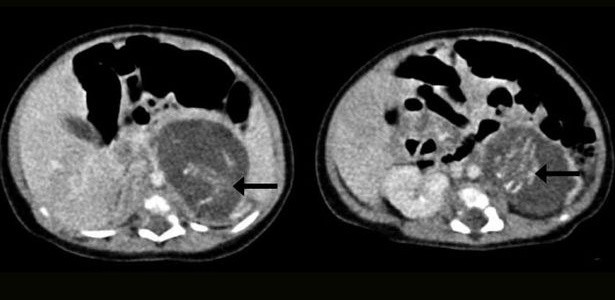

Pode parecer mentira, mas é verdade. Uma recém-nascida de três semanas foi submetida a uma cirurgia para retirar dois pequenos fetos com idade entre oito e dez semanas, que estavam localizados no seu ventre. Este caso invulgar aconteceu em 2010, mas só agora foi divulgado na revista científica “Hong Kong Medical Journal”. De início, os médicos pensaram que a bebé tivesse nascido com um tumor.

Através de ecografias, os médicos conseguiram verificar que os fetos já tinham braços, pernas, costelas, coluna vertebral e intestinos formados. Um tinha 14,2 gramas e o outro 9,3 – cada um com o seu cordão umbilical.

Esta condição, cuja causa é desconhecida, chama-se foetus in fetu (feto dentro de feto, em tradução livre) e ocorre em um a cada 500 mil nascimentos. Menos de 200 casos como este foram registados no mundo.